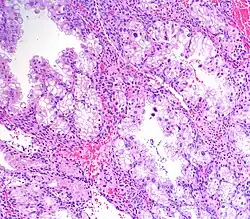

La reacción de Arias Stella o fenómeno de Arias Stella (también se escribe con guion entre los apellidos) consiste en una serie de cambios que ocurren principalmente en el endometrio —la capa más interna del útero— en presencia de tejido coriónico.[1]

Al microscopio óptico, se observan alteraciones en las glándulas del endometrio en varios focos. Las células, y especialmente los núcleos se ven agrandados. Estos pueden mostrar una cromatina de aspecto vacuolizado o granular, aunque también pueden verse núcleos condensados y compactos (o sea, picnóticos). Se han descrito las siguientes variantes histológicas:[2]

- Atipia mínima

- Patrón secretor temprano

- Patrón secretor o hipersecretor

- Patrón regenerativo, proliferativo o no secretor

- Patrón de células monstruosas